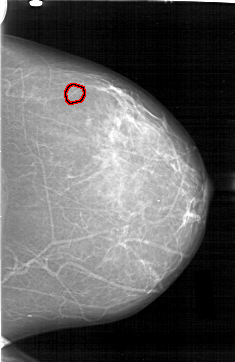

D_4195_1.LEFT_CC

LEFT_CC LINES 6511 PIXELS_PER_LINE 4216 BITS_PER_PIXEL 12 RESOLUTION 43.5 OVERLAY

FILE: D_4195_1.LEFT_CC.OVERLAY

TOTAL_ABNORMALITIES 1

ABNORMALITY 1

LESION_TYPE CALCIFICATION TYPE AMORPHOUS DISTRIBUTION CLUSTERED

ASSESSMENT 0

SUBTLETY 3

PATHOLOGY BENIGN

TOTAL_OUTLINES 1

BOUNDARY